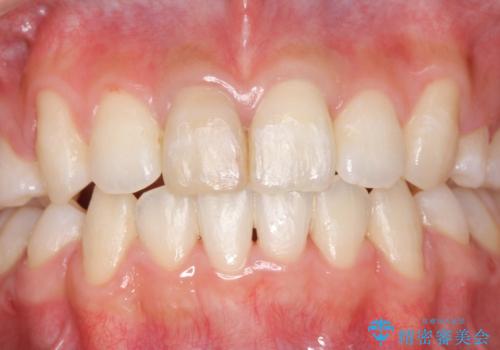

- 患者様

- 10代女子